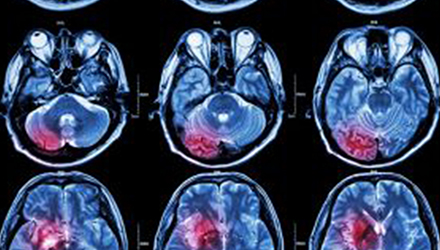

在這項研究中,研究人員使用功能核磁共振成像(fMRI)觀察大腦中血液含氧量的變化。研究人員首先研究了耳鳴患者和無耳鳴者的大腦活動,其目的是比較兩組受試者大腦處理情緒的方式。

在功能磁共振成像檢查中,受試者分別聽30種“愉悅”的聲音、30種“不愉快”的聲音和30種“中性”的聲音。這些聲音包括小孩咯咯笑,嬰兒啼哭,以及熱水壺燒開的聲音。

功能磁共振成像的結果顯示,當暴露于情緒性聲音下,耳鳴患者大腦不同區域的活動比沒有耳鳴者的活動更強烈。接著,研究人員進行了更深入的研究:耳鳴患者的大腦活躍性和耳鳴嚴重程度的關系。

調查結束后,再進行功能核磁共振成像檢查。第二輪功能核磁共振成像顯示,那些耳鳴較輕的患者實際上使用了大腦不同的區域來處理情緒信息。

傳統觀點認為,大腦中的扁桃體是處理情緒的關鍵,但此次研究發現,那些不被耳鳴困擾的患者實際上使用更多大腦額葉來處理情緒。這類患者額葉活動更顯著的原因是,額葉通常更多地用于注意力、計劃和沖動的控制。